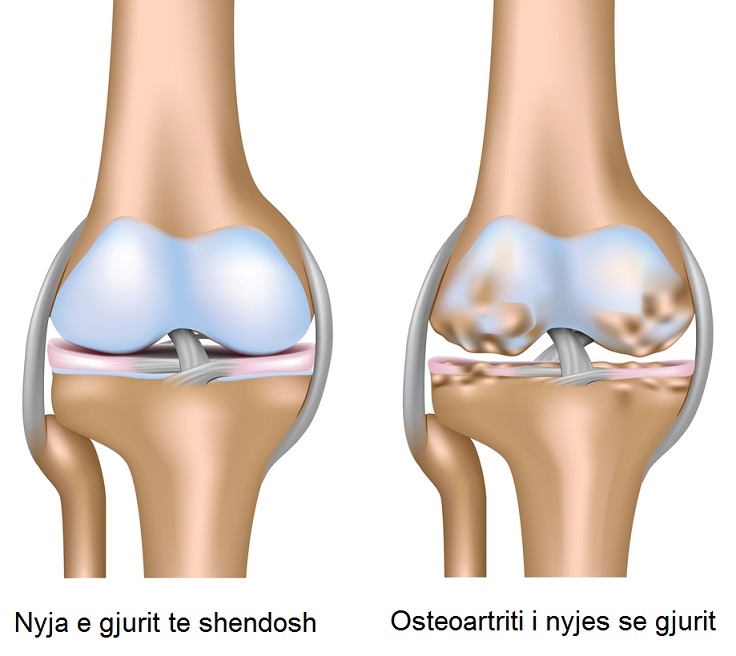

Gonartroza (artroza e gjurit)

Është sëmundja degenerative më e shpeshtë që kap artikulacionin e gjurit. Bëhet fjalë për një konsum të sipërfaqes artikulare të kockave që përbëjnë artikulacionin e gjurit: patela, tibia dhe femuri. Kërci që vesh këto sipërfaqe me kalimin e kohës konsumohet, hollohet deri sa del kocka që është nën të. Gonartroza është një sëmundje tipike e …